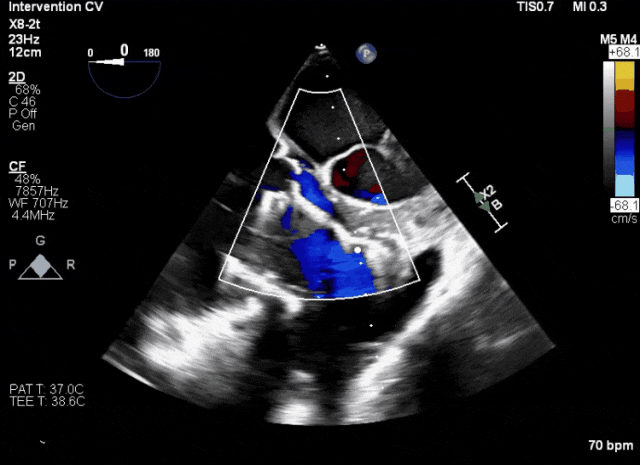

近日,健世科技(9877.HK)自主研發(fā)的經(jīng)頸靜脈三尖瓣置換產(chǎn)品LuX-Valve Plus在亞太地區(qū)多家醫(yī)院成功完成了一系列收費同情救治使用,其中包括數(shù)例罕見復雜解剖結(jié)構(gòu)的病例。術(shù)后患者臨床表現(xiàn)、心臟功能及生活質(zhì)量顯著改善,充分證明了該產(chǎn)品適用范圍廣、可靠性高及操作簡單的特點。

堅守自主創(chuàng)新,歷經(jīng)十載研發(fā)之路,健世科技成功開發(fā)出LuX-Valve及LuX-Valve Plus經(jīng)導管三尖瓣置換產(chǎn)品,為三尖瓣重度反流這一公共健康危機和全球性難題交上了令人振奮的解決方案。面對患者們急迫的臨床治療需求,健世科技正在持續(xù)快速開展LuX-Valve Plus于亞太地區(qū)的收費同情救治使用手術(shù),提前實現(xiàn)對重度三尖瓣反流患者的救治。

手術(shù)過程

術(shù)者采用經(jīng)右側(cè)頸靜脈入路的方式將輸送器送入患者心臟內(nèi),在TEE及DSA引導下調(diào)整輸送器頭端角度,使得輸送器與三尖瓣瓣環(huán)平面垂直。在輸送器進入右心室后釋放室間隔錨定裝置,而后釋放瓣葉夾持件(2個耳片結(jié)構(gòu))成垂直狀態(tài)。在TEE及DSA確定夾持件固定至三尖瓣葉根部且位于右室側(cè)后釋放人工瓣心房側(cè)盤片。隨后調(diào)整瓣膜同軸性以及室間隔錨定件位置(貼合室間隔),前推藏針管并固定,進而釋放室間隔錨定裝置,并再次確認瓣膜位置、穩(wěn)定性及同軸性,合攏輸送鞘后撤出輸送器,最終順利完成LuX-Valve Plus人工三尖瓣瓣膜的植入。

術(shù)后,各大醫(yī)院教授術(shù)者均夸贊LuX-Valve Plus產(chǎn)品選擇性及包容性強,容錯率高,特別是對于大瓣環(huán),可以滿足更多需求,解決現(xiàn)有臨床難題,給患者帶來福音,有效地改善和提高患者的生活質(zhì)量。